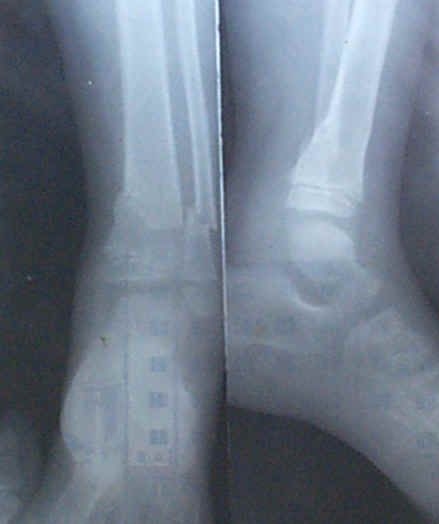

病例:李如祥

李如祥,男,出生于1994年11月29日,住江西万载县罗城乡麻田村庙前小组。1999年1月25日被柴压伤左脚,当天来我处治疗,我用手法先使折骨复位,贴一张小号膏药包扎固定。当天去三兴卫生院摄片诊断左脚胫骨、腓骨骨折。用药二次,每次一张小号膏药,一个月后能用拐杖行走,四个月后恢复正常。此病例治疗时间较长,用药量小,每次用的是小号膏药。